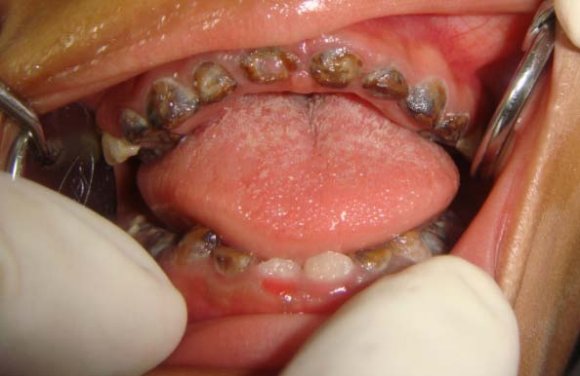

OSMF was found to be predominant in females 16 . The mean age was 43 years. Burning sensation and discomfort in the oral mucosa during mastication was the most common complaint amongst the reported cases. There is associated depapillation of the tongue (Fig: 1). Progressive changes including difficulty in mastication, reduced salivation, dysphasia, pain in the ears and loss of auditory acuity due to stenosis of the pharyngeal end of Eustachian tubes.

In advanced cases, the jaws become inseparable and totally inelastic and plastic and nutrition can be maintained only by pushing the food into mouth. The buccal mucosa is frequently ulcerated and secondarily infected consequent to ischemia and constant pressure of the mucosa against the buccal aspect of the teeth.

Pindborg provided staging criteria for OSMF 20 . He divided the stages according to the clinical presentation of the disease as: Early lesions demonstrate blanching of oral mucosa and older lesions presents with vertical and circular palpable fibrous bands in the buccal mucosa and around the mouth opening or lips, resulting in mottled, marble like appearance(Fig: 4) of the mucosa.

This stage is characterized by reduced mouth opening, stiff and small tongue, fibrotic and depigmented gingiva, shrunken bud like uvula.